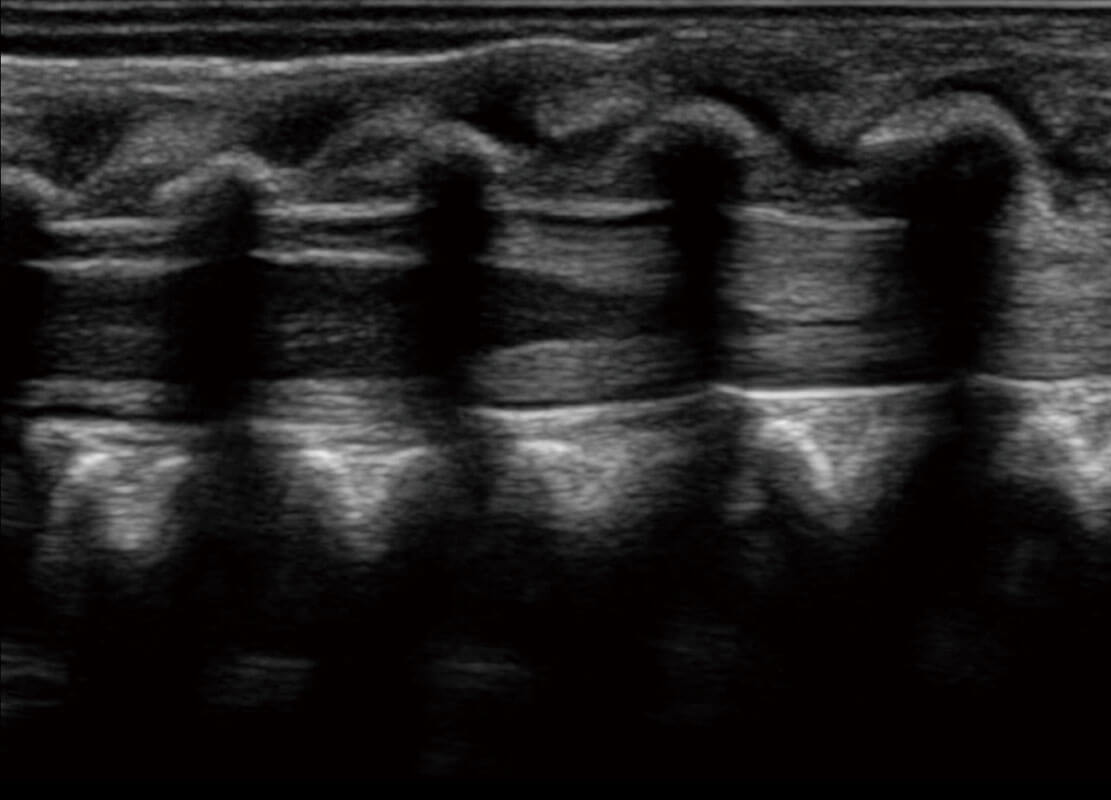

乳腺超声 / 新生儿

P60搭载宽频带线阵探头、宽景成像、弹性成像技术,为您提供乳腺应用方案。P60支持高频相控阵探头、线阵探头、腹部高频探头、腹部微凸探头等,丰富的探头群搭载敏感的彩色血流成像,适用于新生儿多种脏器检测要求,满足新生儿筛查需求。

• 新生儿心脏